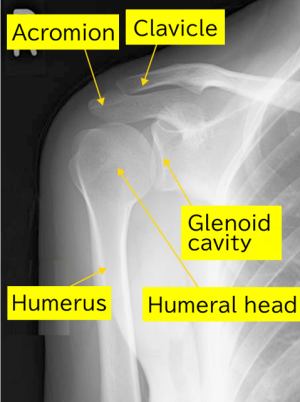

【Normal, Preoperative and Postoperative X-rays for Total Shoulder Arthroplasty】

Normal

The humeral head has a rounded shape, and there is a space between the glenoid cavity and the humeral head.

Preoperative X-ray:

Significant deformation of the humerus is observed. The round shape of the humeral head is lost.